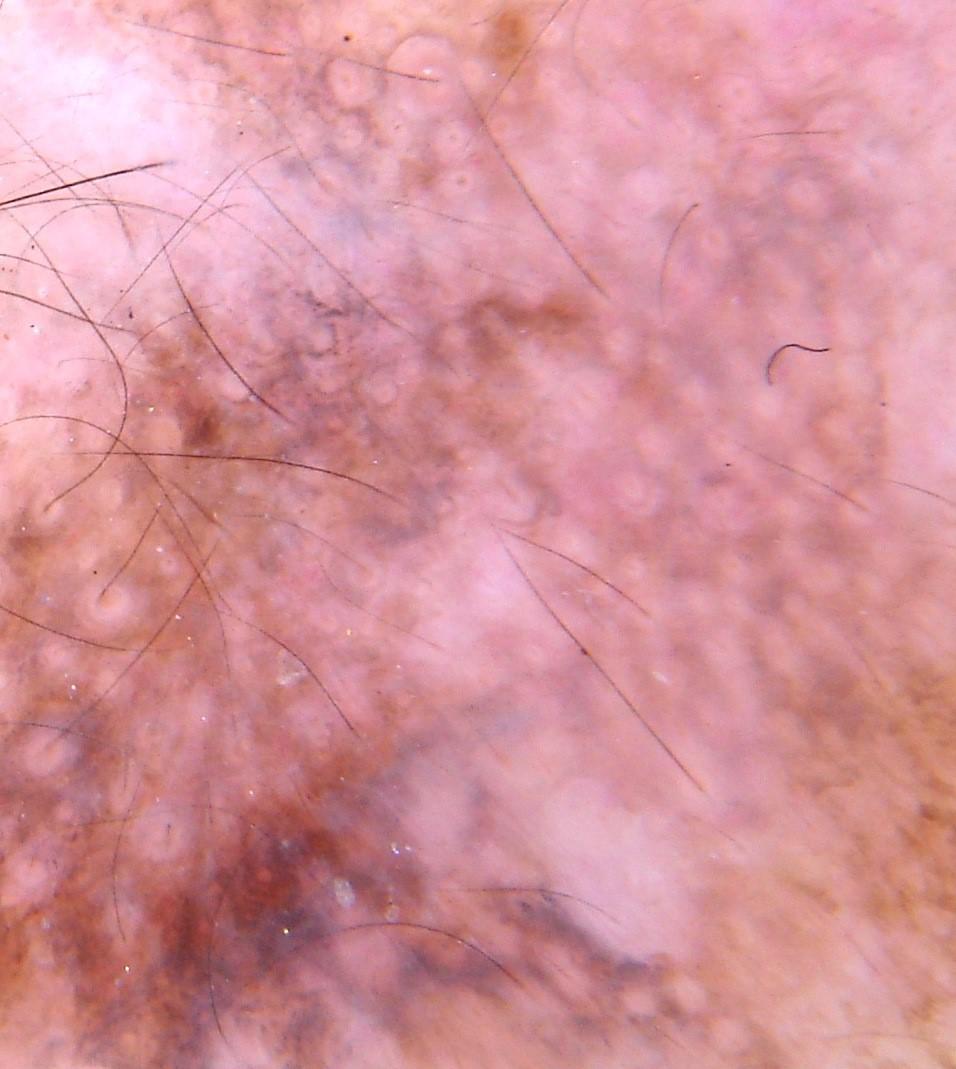

{

"age_approx": 85,

"anatom_site_general": "lower extremity",

"concomitant_biopsy": true,

"dermoscopic_type": "non-contact polarized",

"diagnosis_1": "Malignant",

"diagnosis_2": "Malignant melanocytic proliferations (Melanoma)",

"diagnosis_3": "Melanoma in situ",

"diagnosis_confirm_type": "histopathology",

"family_hx_mm": false,

"image_type": "dermoscopic",

"mel_thick_mm": "0.00",

"melanocytic": true,

"patient_id": "IP_9183698",

"personal_hx_mm": false,

"sex": "male"

}